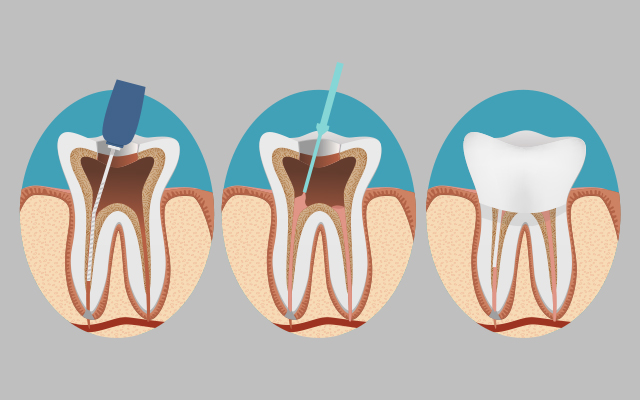

Pulpotomías: Tratamiento parcial de la pulpa dental en dientes de leche, donde se retira únicamente la parte afectada y se sella con un agente biocompatible para conservar la función y evitar extracción.

Pulpectomías: Endodoncia completa en dientes temporales muy dañados, que consiste en limpiar y desinfectar todo el conducto radicular, luego rellenarlo con material reabsorvible hasta la caída natural del diente.